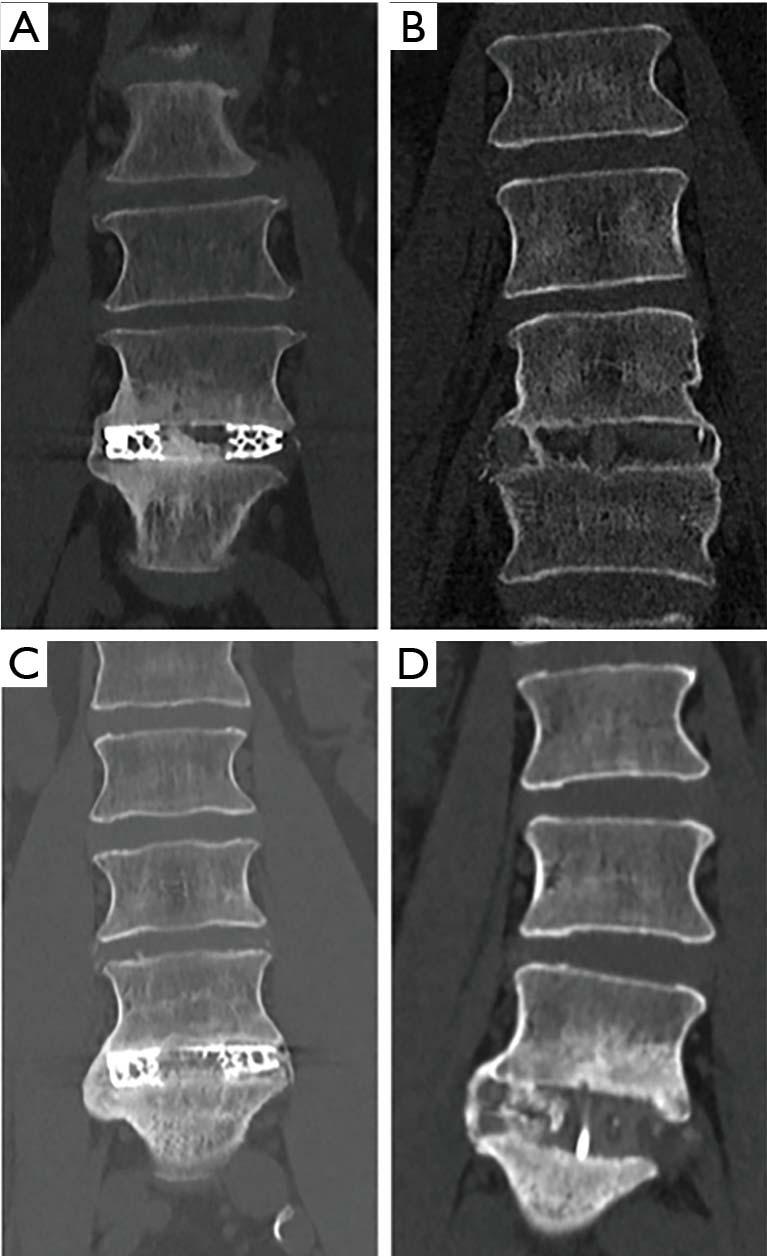

A retrospective study of patients undergoing SA-LLIF with 3D-printed Ti cages and PEEK cages between 11/2016 and 01/2020 at a single academic institution was done. Fusion was assessed for each treated level using multiplanar reconstructed computed tomography (CT) scans. Presence of fully bridged interbody trabecular bone or continuous bone centered in the cage was considered as fusion.

In total, 91 patients (136 levels) were included in the final analysis, 49 patients (72 levels) in the early group and 42 patients (64 levels) in the late group. CT scans were performed on average 8.2±1.8 months postoperatively for the early group and 18.9±7.7 months for the late group. In the early group, fusion was significantly higher for 3D-printed Ti cages compared to PEEK cages (95.8% versus 62.5%; P=0.002), whereas in the late group no significant difference was seen (94.7% versus 80.0%; P=0.258).

In SA-LLIF, porous 3D-printed Ti cages showed significantly higher fusion rates at an early timepoint compared to PEEK. However, the difference in fusion rates between 3D-printed Ti cages and PEEK cages was found not to be significantly different at a later timepoint in another patient group. This might support the assumption that 3D-printed Ti cages with a porous architecture are more osteoconductive compared to PEEK and tend to fuse earlier.

对2016年11月至2020年1月期间在单一学术机构接受SA - LLIF并使用3D打印Ti笼和PEEK笼的患者进行回顾性研究。使用多平面重建计算机断层扫描(CT)对每个治疗节段的融合情况进行评估。椎间小梁骨完全桥接或笼中心连续骨的存在被视为融合。

最终分析共纳入91例患者(136个节段),早期组49例患者(72个节段),晚期组42例患者(64个节段)。早期组术后平均8.2±1.8个月进行CT扫描,晚期组为18.9±7.7个月。在早期组中,3D打印Ti笼的融合率显著高于PEEK笼(95.8%对62.5%;P = 0.002),而在晚期组中未观察到显著差异(94.7%对80.0%;P = 0.258)。

在SA - LLIF中,与PEEK相比,多孔3D打印Ti笼在早期显示出显著更高的融合率。然而,在另一患者组的后期时间点,发现3D打印Ti笼和PEEK笼之间的融合率差异无统计学意义。这可能支持以下假设,即具有多孔结构的3D打印Ti笼比PEEK具有更高的骨传导性,并且倾向于更早融合。